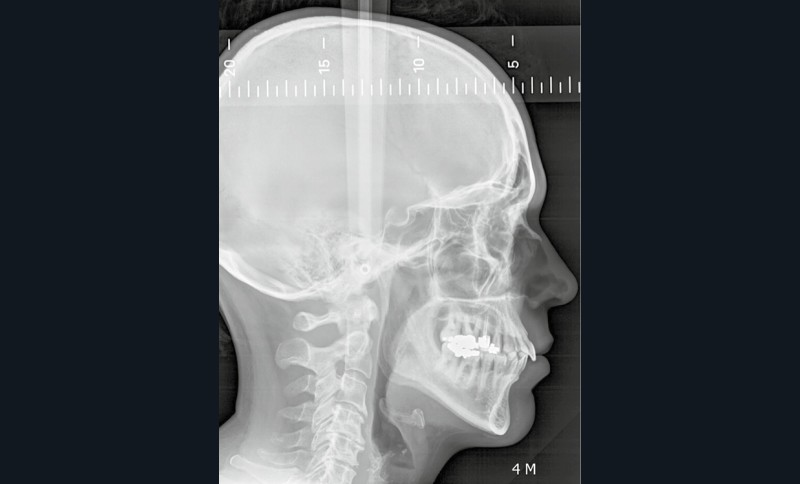

L’examen radiographique (fig. 3-5) nous indique une Classe I squelettique de Ballard (ANB 0°) sur un schéma facial à tendance hyperdivergent (FMA 28°). L’analyse céphalométrique confirme la vestibulo-version incisive (I/SN 111° ; IMPA 94°). La lyse osseuse est généralisée.